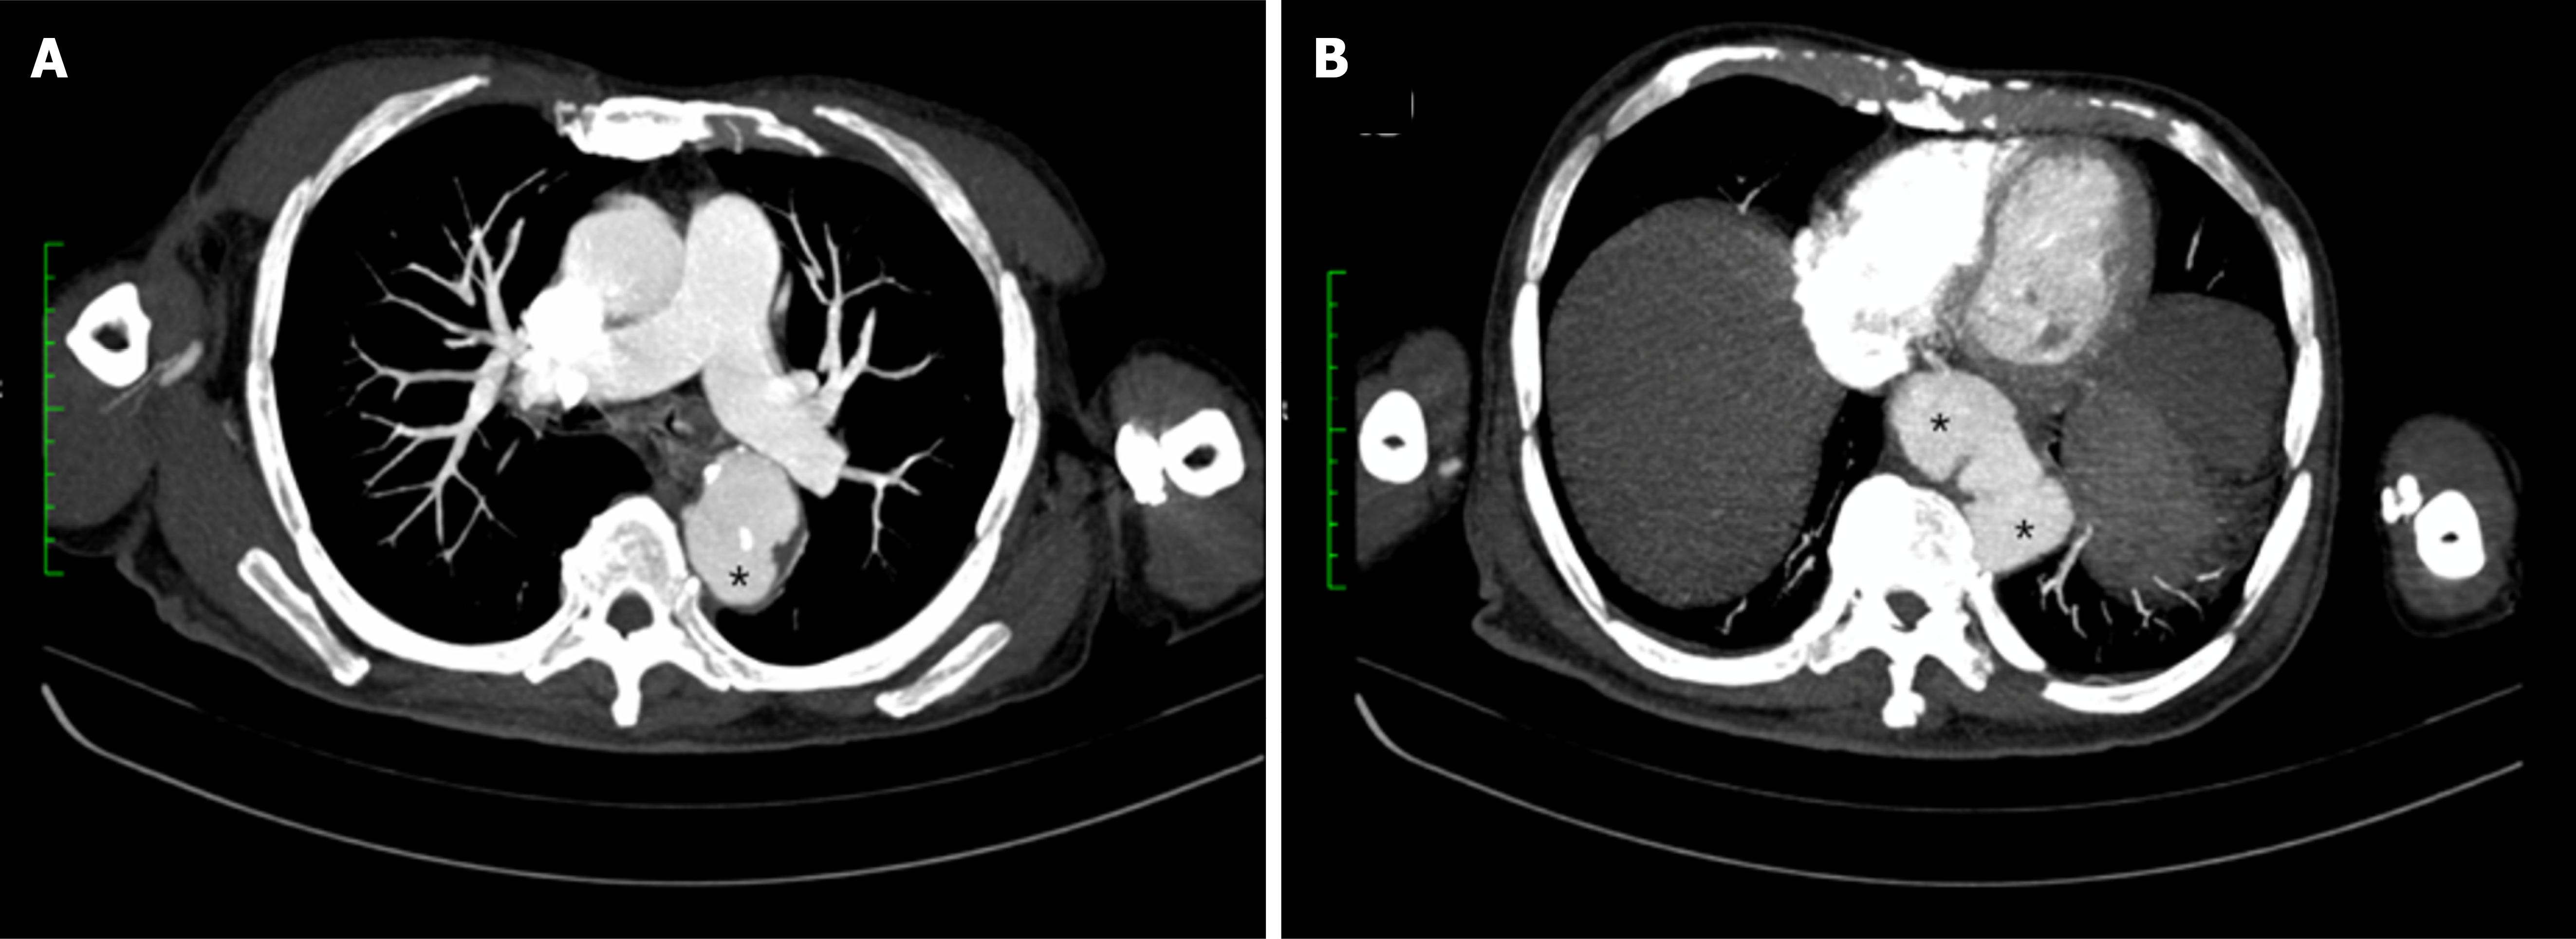

Figure 2 Axial view of computed tomography angiography of the thoracic aorta.

A: Upper thoracic axial section demonstrating a saccular aneurysm (*) arising from the descending thoracic aorta; B: Lower thoracic axial section showing additional saccular aneurysms (*) along the descending thoracic aorta.